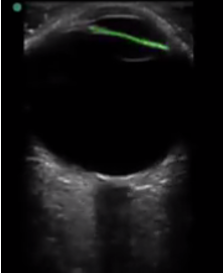

Bild: Augen, Markierung der Iris

Markierter Bereich: Iris